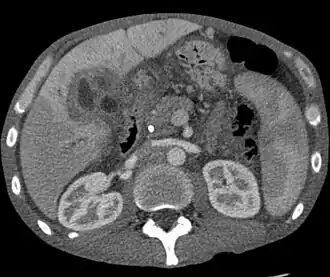

| Tomografia de um colangiocarcinoma. | |